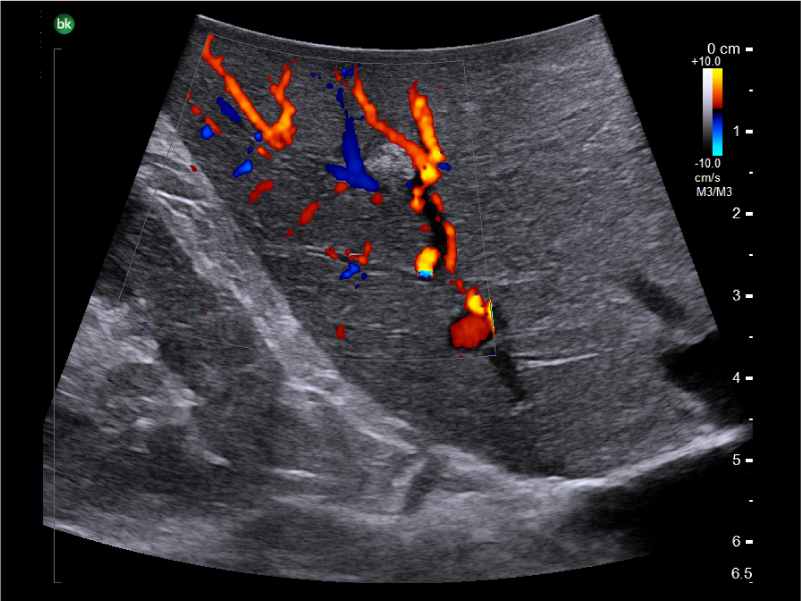

Small metastatic liver lesion with color Doppler, visualized with T-Shaped Transducer

Active imaging

with intraoperative ultrasound supports critical decision-making in open or minimally invasive tumor resections.